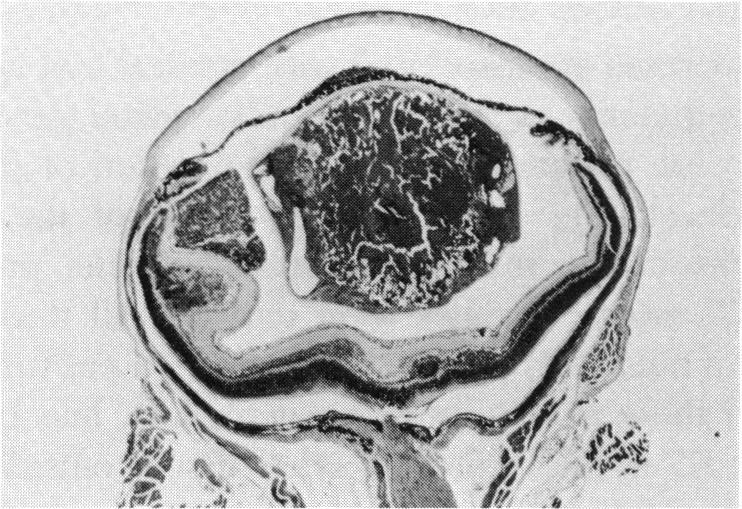

Transgenic models of retinoblastoma: what they tell us about its cause and treatment.

Trans Am Ophthalmol Soc. 1994;92:385-400; discussion 400-1.

PMID:7886874

原文链接:https://pmc.ncbi.nlm.nih.gov/articles/PMC1298518/